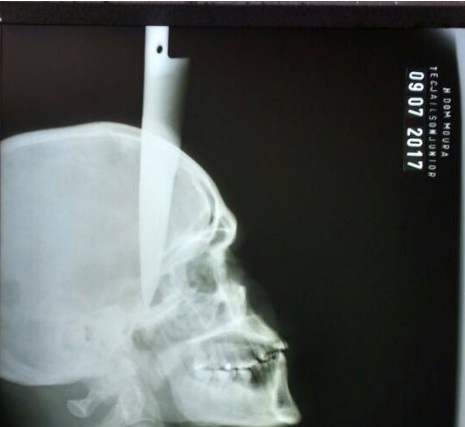

Homem sofre atentado e fica com faca cravada na cabeça em Garanhuns - PE.

Um homem identificado como José de Ailton, 35 anos,

sofreu uma tentativa de homicídio em Garanhuns, no Agreste do Estado e

foi levado para o Hospital da Restauração, na área central do Recife,

com uma faca cravada na cabeça. De acordo com a Polícia Militar, o homem

foi esfaqueado após uma discussão enquanto bebia com o suspeito do

crime, na noite desse domingo (9), na Zona Rural da cidade.

Inicialmente, entre 21h e 22h do domingo (9), o homem, que também

estava com ferimentos no braço direito, e no tórax, foi socorrido para o

Hospital Dom Moura, em Garanhuns. Por volta das 22h40, ele foi

transferido para o Hospital da Restauração, onde passa por procedimento

cirúrgico, na manhã desta segunda (10).